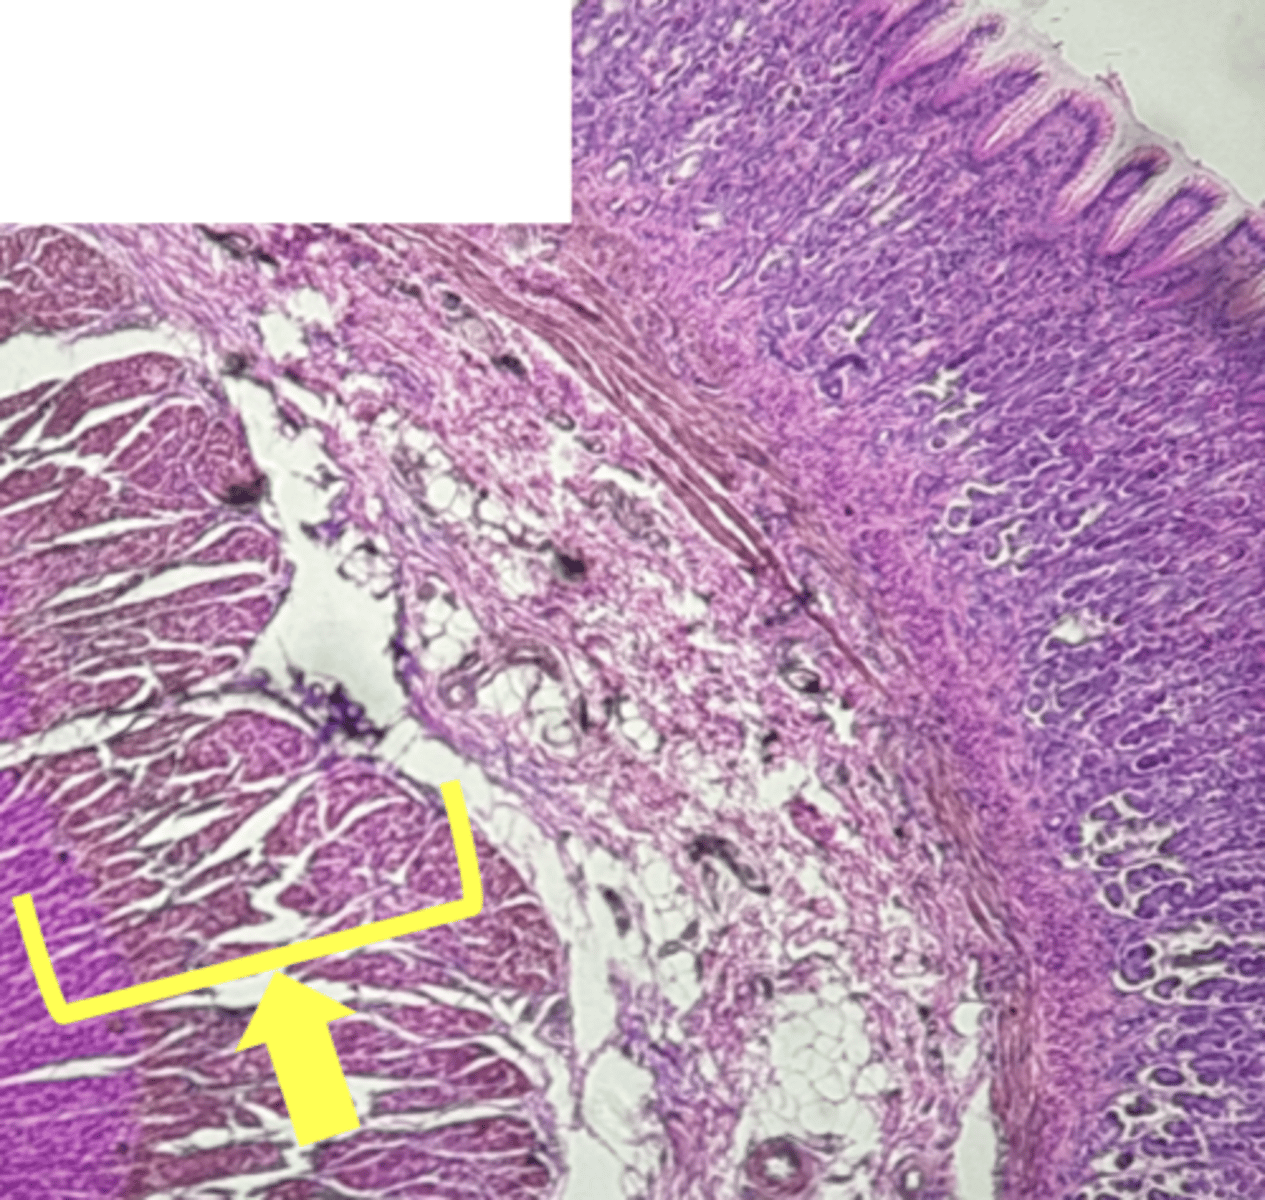

A- Esophagus

B- Stomach

Name the Tissue A & B

stomach

name the tissue

mucosa

(stomach)

submucosa

muscularis externa (3 LAYERS-KEY CHARACTERISTIC)

oblique layer

circular layer

longitudinal layer

simple columnar epithelium

gastric pits (KEY CHARACTERISTIC)

gastric glands (KEY CHARACTERISTIC)

Parietal cells- HCl (hydrochloric acid)

name the cell & what it secretes

Chief Cells- pepsinogen/pepsin

Lamina propria

muscularis mucosae

Esophagus

(esophagus)

muscularis externa

stratified squamous epithilium (KEY CHARACTERISTIC)